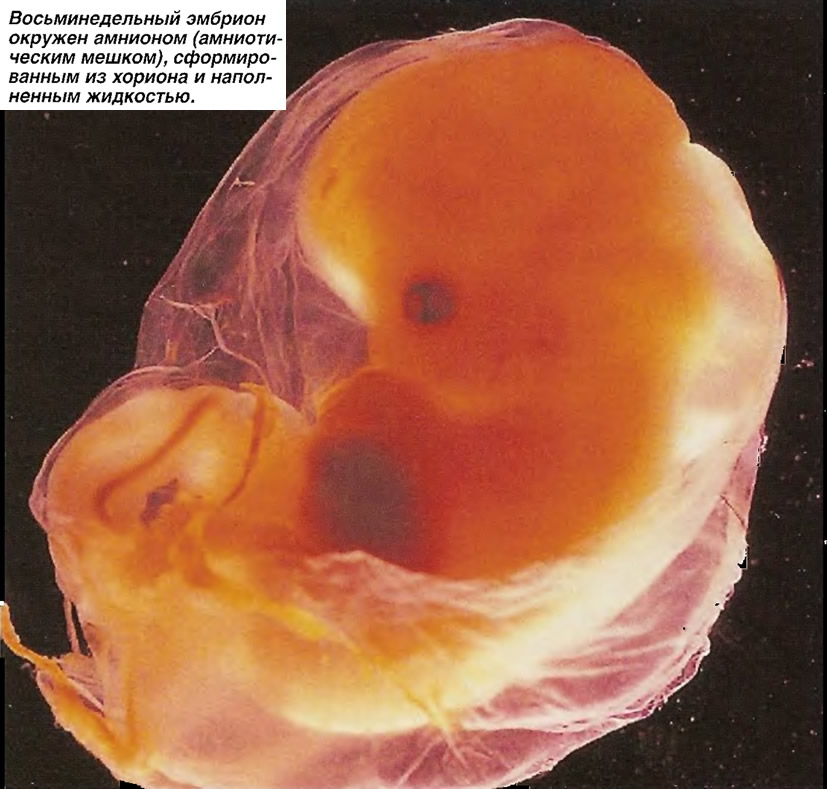

Удивительные фотографии эмбриона на 8 неделе беременности